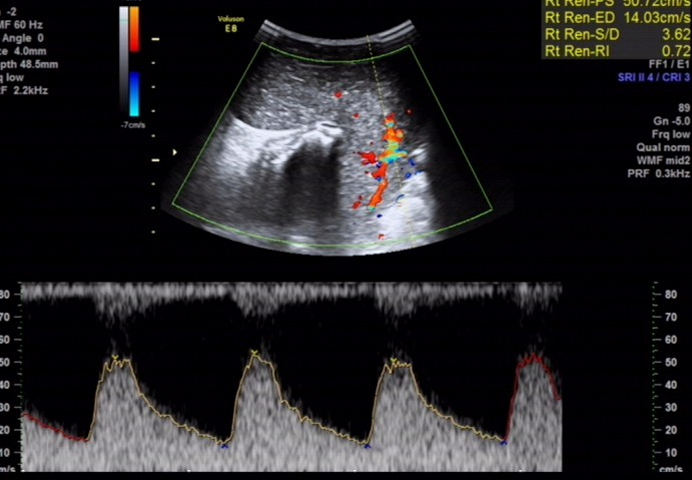

骶尾部皮下软组织层内探及一范围约 145×98×107mm 的低回声包块,围绕骶骨生长,部分向盆腔内生长,与周围其他组织分界清楚,内部回声欠均匀, CDFI:内见多个条状血流信号, PW 检测:呈动脉频谱, RI:0.72 。

图 4 PW检测呈动脉频谱, RI:0.72